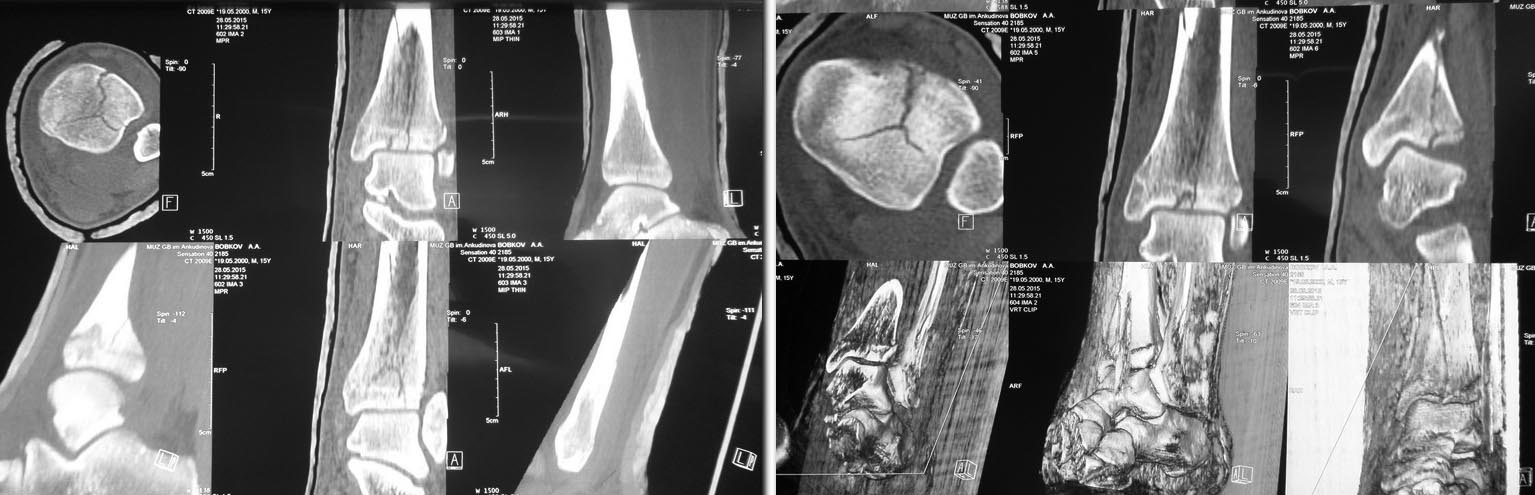

Сделал КТ контроль. Можно обойтись 3 винтами. В области эпифиза: 1

спонгиозный стягивающий винт провести снаружи кнутри, 2 стягивающий

спонгиозный винт спереди назад и немного изнутри кнуаружи. На диафизе 1

кортикальный стягивающий винт. После операции 3 недели гипсовой

иммобилизации, после чего рентген контроль и начинать постепенную

поэтапную нагрузку на оперированную конечность. Сперва ходить 2 - 3

недели с нагрузкой "контакт с полом" + активное ЛФК с инструктором,

затем еженедельно повышать нагрузку на 15% от массы тела, через 6 недель

рентген контроль и ходить при помощи трости 1 месяц. Если поставить

пластину, то срок консолидации будет такой же, но нагрузку можно давать

раньше. Джолдас, можете прокоментировать. Заранее благодарен.